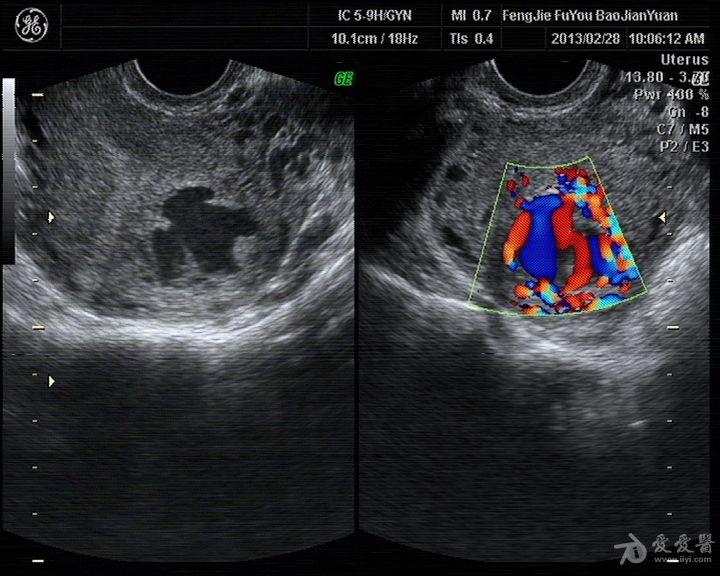

[妇科] 葡萄胎清宫术后复查

葡萄胎清宫

葡萄胎